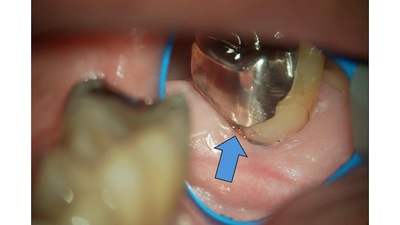

なぜ「銀歯」の下は虫歯になりやすい?顕微鏡で見るとわかる「適合精度」の決定的な違い